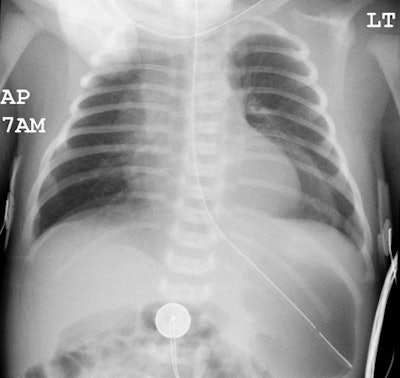

Unsuspected congenital diaphragmatic hernia: The newborn shown below presented with respiratory difficulty, but did not have a scaphoid abdomen. The frontal CXR demonstrated and abnormal lucency and curvilinear density in the left base. A lateral view revealed findings concerning for a diaphragmatic hernia. This was confirmed on CT imaging- note that a portion of the stomach and the spleen have herniated through the defect. |